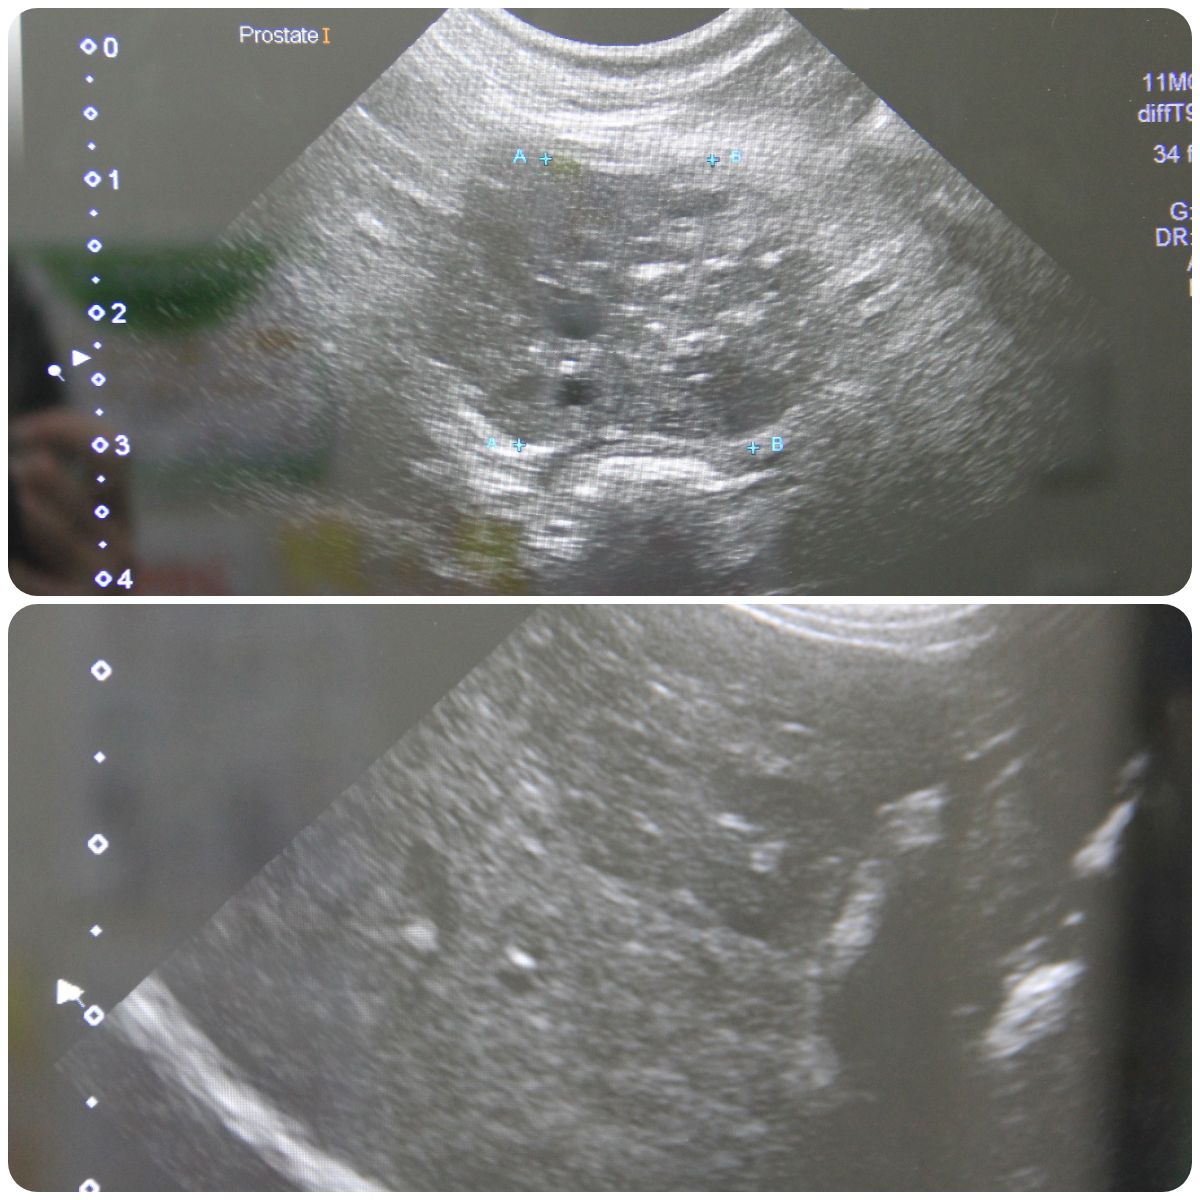

気になることがあって病院で診察だ ▼・。・▼… 2025年10月19日